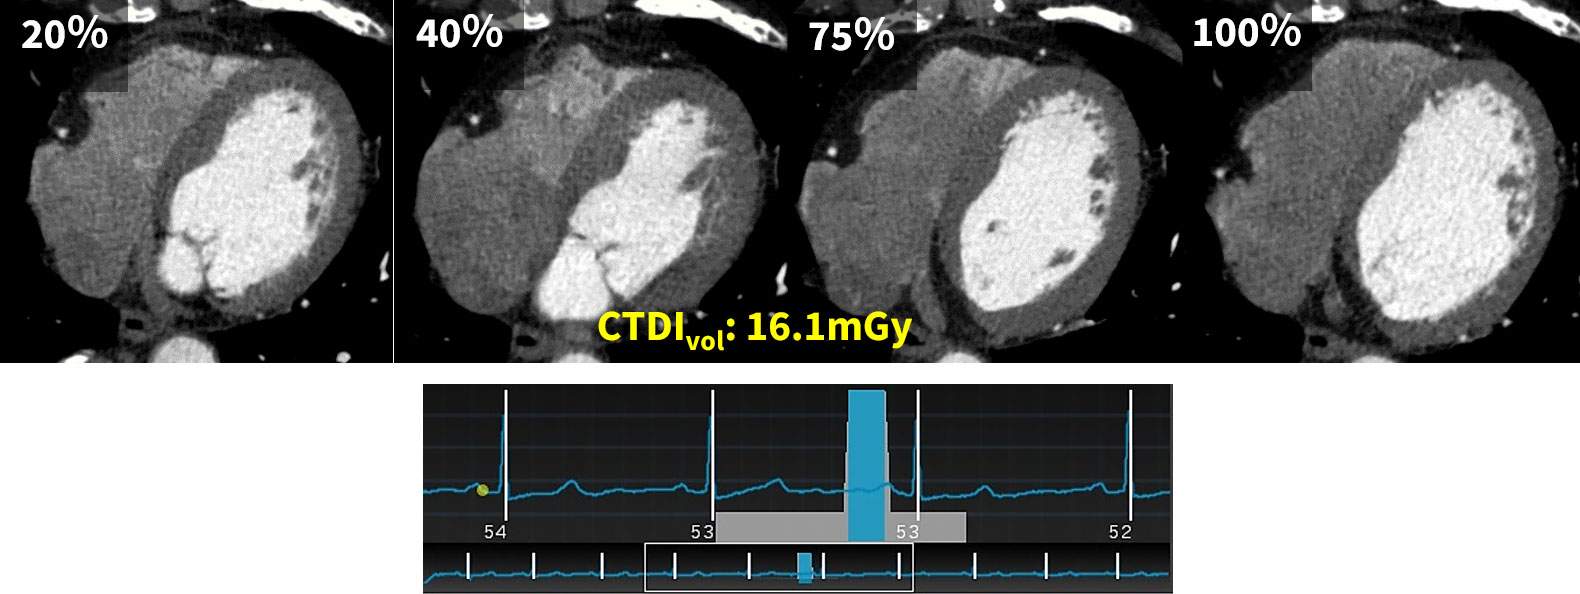

Auto Gating機能をオフにしてマニュアル設定を行うケースもあり、被曝をさらに低減するためにターゲット心位相を75%に限定したり(図1)、壁運動の情報が必要な場合には1心拍の部分をターゲット心位相以外で線量50%以下に設定することで(図2)、目的に応じた撮影を目指しています。

RevolutionApexElite_Minaminojunkanki04.jpg

(図2)ターゲット心位相75%と線量50%低減の0-110% CTDIvol:16.1mGy